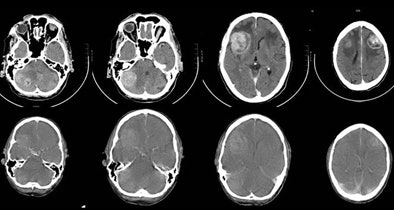

| A 67-year-old man with small cell lung cancer in the left upper lobe also developed neurological symptoms. Diagnostic brain CT (upper row) showed multiple brain metastases: two right cerebellar, one right frontal, and one left frontal, all surrounded by edema. The CT component of the integrated PET/CT (lower row) also showed brain metastases but could not demonstrate one right cerebellar metastasis (first image). The quality of the CT of the PET/CT is inferior to that of diagnostic brain CT. There is reduced contrast opacification and the surrounded edema is not clearly visualized, although this could have been due to the treatment with corticosteroids in the short time between diagnostic brain CT and integrated PET/CT. All images and charts courtesy of Dr. Walter De Wever. |